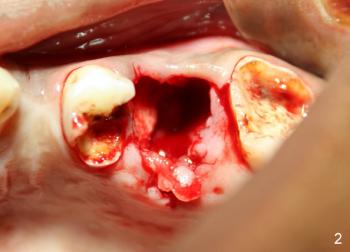

If left untreated, bacteria will continue to invade deeper into the tooth structure — eventually reaching the pulp, which contains nerves and blood vessels. This can lead to pain, infection, or even abscess formation.

Possible Complications if Ignored:

Increased tooth sensitivity and pain

Deep pulp infection requiring root canal treatment

Swelling or abscess formation

Eventual tooth loss if decay spreads below the gum line